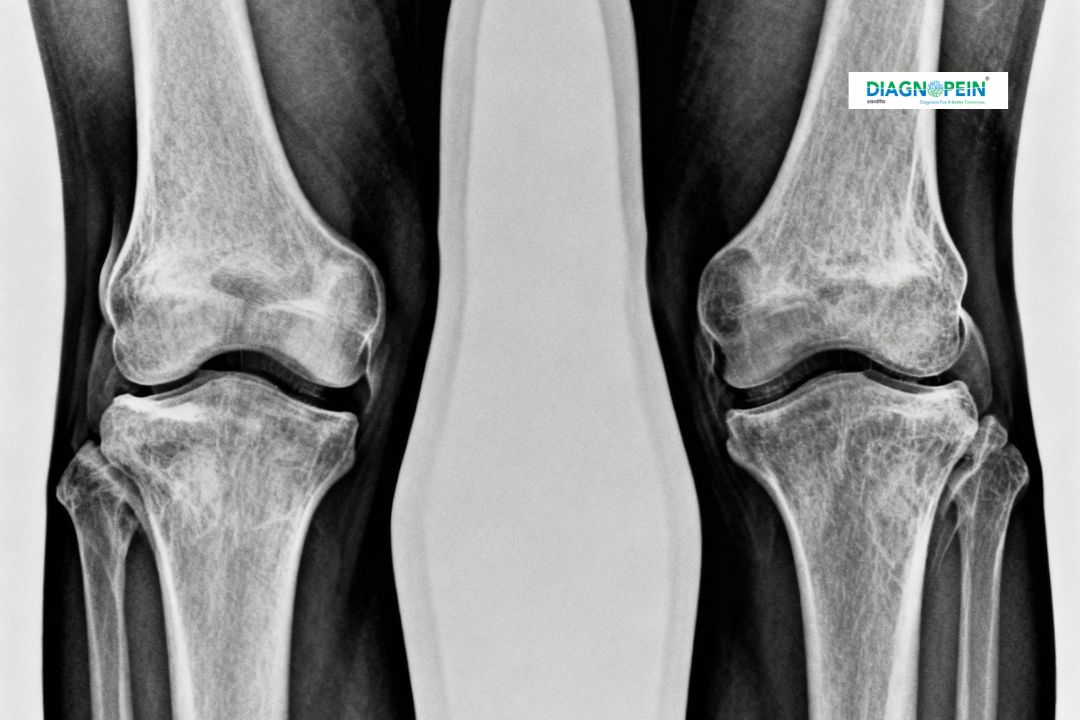

At Diagnopein in Karad, we provide precise and advanced X-Ray Both Knee Standing AP View imaging to help doctors accurately evaluate your knee joint structure and alignment. This diagnostic X-Ray technique captures a frontal (anterior-posterior) view of both knees while you stand upright. It allows assessment of how your knees align under natural body weight, which is crucial for understanding joint spacing, bone condition, and any degenerative changes.

An X-Ray Both Knee Standing AP View plays an important role for individuals dealing with pain, stiffness, osteoarthritis, ligament injuries, or suspected joint deformities. Because both knees are imaged together, your orthopedic specialist can compare them directly for a better diagnosis.

The importance of getting an X-Ray Both Knee Standing AP View in Karad lies in its ability to show real-time structural alignment under normal weight-bearing conditions. This view is essential for:

1. Evaluating the knee joint space between the femur and tibia

2. Identifying osteoarthritis, cartilage loss, and bone deformities

3. Assessing joint alignment and symmetry in standing posture

4. Planning orthopedic treatments such as knee replacement or corrective surgery

5. Detecting early signs of rheumatoid arthritis or joint degeneration

During the X-Ray Both Knee Standing AP View, the following parameters are assessed:

1. Joint space width between femur and tibia

2. Tibiofemoral and patellofemoral alignment

3. Bone density and surface appearance

4. Signs of osteoarthritis or chondromalacia

5. Varus or valgus deformity detection